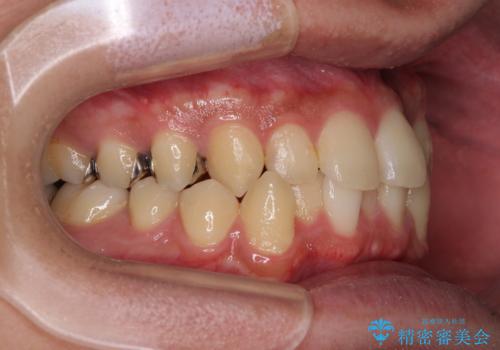

- 上下のクロスバイトと前歯のデコボコを気にして来院された患者様です。

インビザラインを用い、IPR(歯と歯の間を削る)と歯列全体を拡大させることで、歯並びを整えていくこととしました。

インビザライン特有の、治療後半に奥歯が咬み合わないという事象が長引きました。

咬み合わないときの対処方法は色々とありますが、ゴムかけなどを活用して噛めるようにしました。